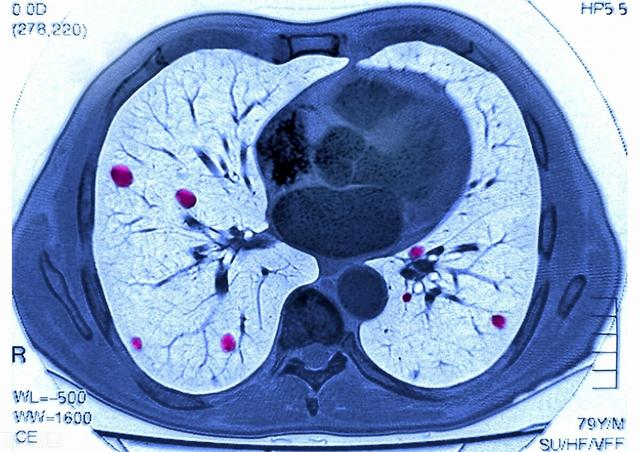

1) L'insuffisance respiratoire, communément appelée manque d'air du patient, est la plus fréquente chez les patients atteints d'un cancer du poumon avancé. Le cancer central du poumon obstrue la trachée et les bronches principales, ce qui rend difficile l'entrée de l'air, et en cas d'atélectasie pulmonaire importante, le patient souffrira progressivement d'essoufflement et de dyspnée. Certains patients développent un épanchement pleural important dû à des métastases pleurales, qui comprime les tissus pulmonaires et empêche la réouverture des poumons. Chez d'autres patients, les lésions pulmonaires sont trop nombreuses et la surface effective de la membrane respiratoire est considérablement réduite. Toutes ces raisons finissent par entraîner une oppression thoracique, un essoufflement, une respiration assise et, finalement, une insuffisance respiratoire.

La plupart des cancers du poumon avancés forment des métastases dans le foie, le cerveau et les os et peuvent entraîner la défaillance d'un organe.

À un stade avancé, le cancer du poumon peut présenter de multiples métastases dans divers organes du corps. Le cancer du poumon métastase souvent dans le cerveau, le foie et le système vertébral squelettique, et les métastases cérébrales peuvent provoquer une hypertension intracrânienne. L'espace étant limité dans le cerveau, la propagation des cellules cancéreuses peut entraîner une hernie cérébrale et une hypertension intracrânienne, qui mettent en danger la vie du patient. Les métastases vertébrales peuvent entraîner des fractures pathologiques, une compression des nerfs, conduisant à la paralysie et même à la mort. Des métastases hépatiques multiples, qui peuvent entraîner un dysfonctionnement du foie et une insuffisance hépatique.

4. métastases tumorales, défaillance de plusieurs organes :Des métastases à différents organes peuvent se produire à un stade avancé du cancer du poumon, causant de grandes souffrances aux patients. Les patients atteints de cancer du poumon peuvent former des métastases dans des organes tels que la plèvre, le cerveau, les glandes surrénales, le foie, les os, le péricarde et ainsi de suite, provoquant une défaillance de plusieurs organes, qui peut entraîner la mort du patient.

Des études montrent qu'en 2012, environ 1,8 million de nouveaux cas de cancer du poumon ont été recensés dans le monde, entraînant environ 1,6 million de décès.